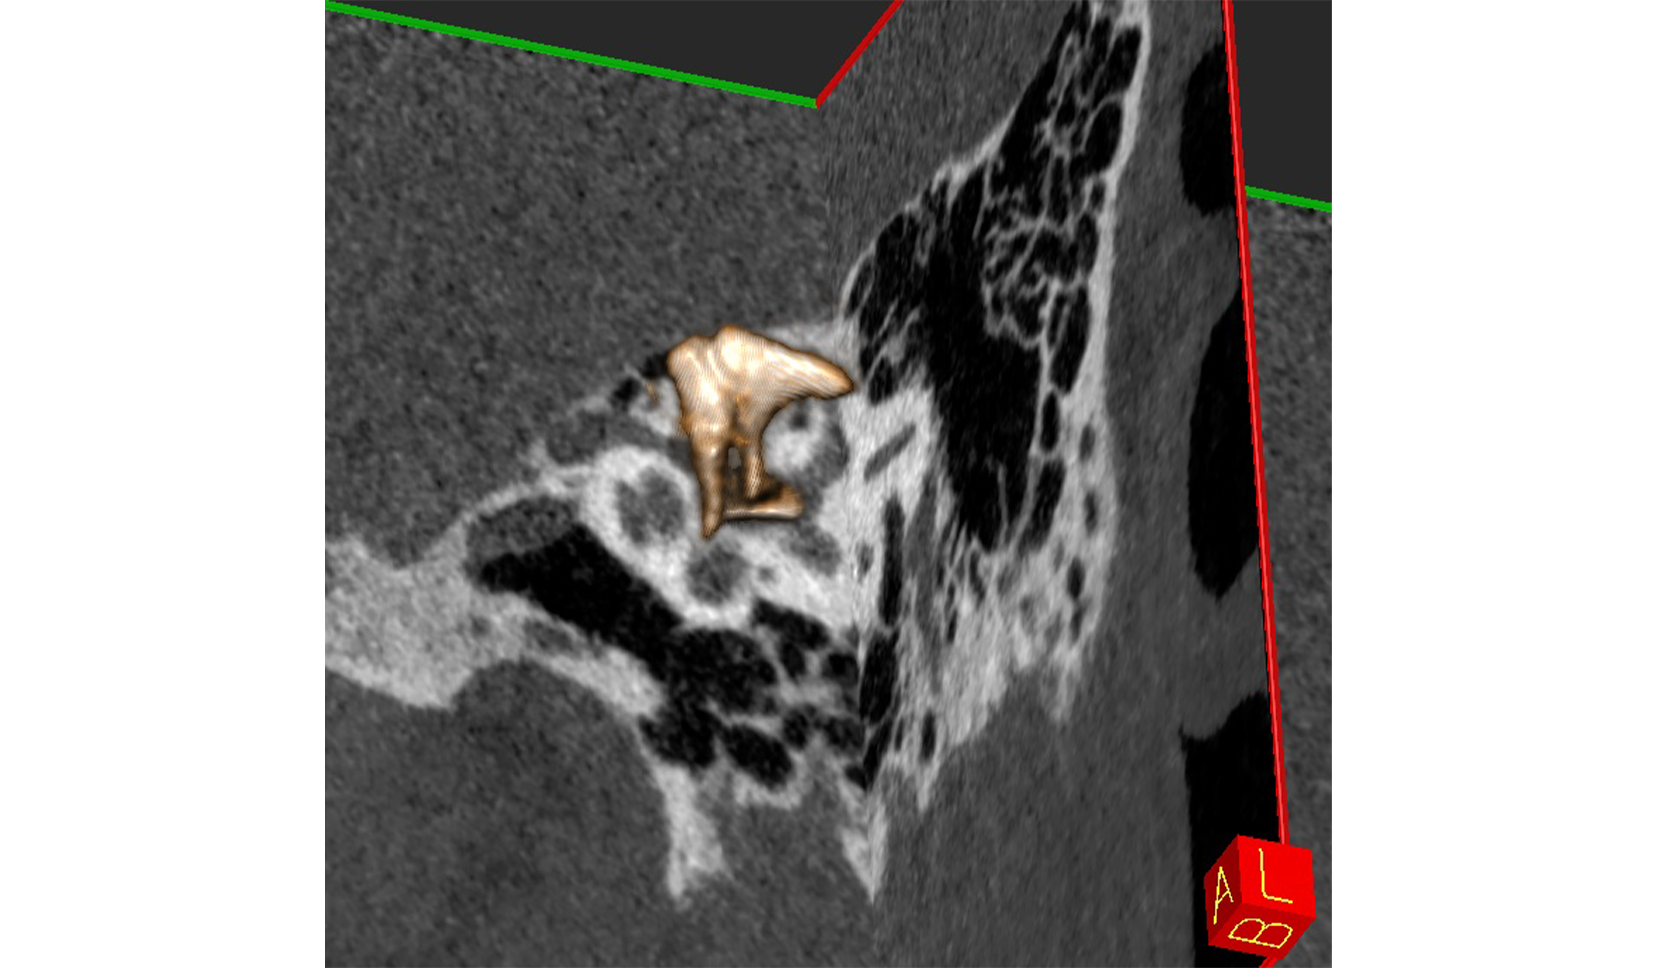

Oido

Cadena Osicular DER IZQ

Oído Interno (Cóclea y Canales Semicirculares) DER IZQ